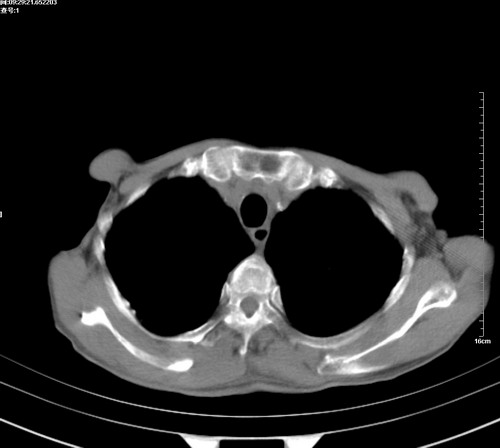

病人,女,79岁,主要因腹疼二月入院,彩超,肝,胆,脾,未见异常,胸透上消化道造影未见异常,化验白细胞增高,内科医生让做胸部ct检查,因为熟人多做了腹部(外科会诊考虑胆囊炎).现ct片如下请假各位战友.

中后纵隔占位,气管、食道受压、变形、移位。恶性可能性大。

考虑:中后纵隔转移瘤可能性大,主动脉硬化。

纵隔淋巴结肿大,考虑转移而来

中后纵隔转移瘤可能性大,主动脉硬化。

后中纵隔团块影,伴气管、食道受压移位,首先考虑转移瘤,肝s5段低密度灶。建议增强检查,另外其结肠是否有问题请提供,右肺部分肺叶局限含气增多,考虑局限肺气肿。

建议强化检查,考虑纵隔型肺癌,小细胞可能性大。

后中纵隔淋巴结肿大,首先考虑转移瘤。